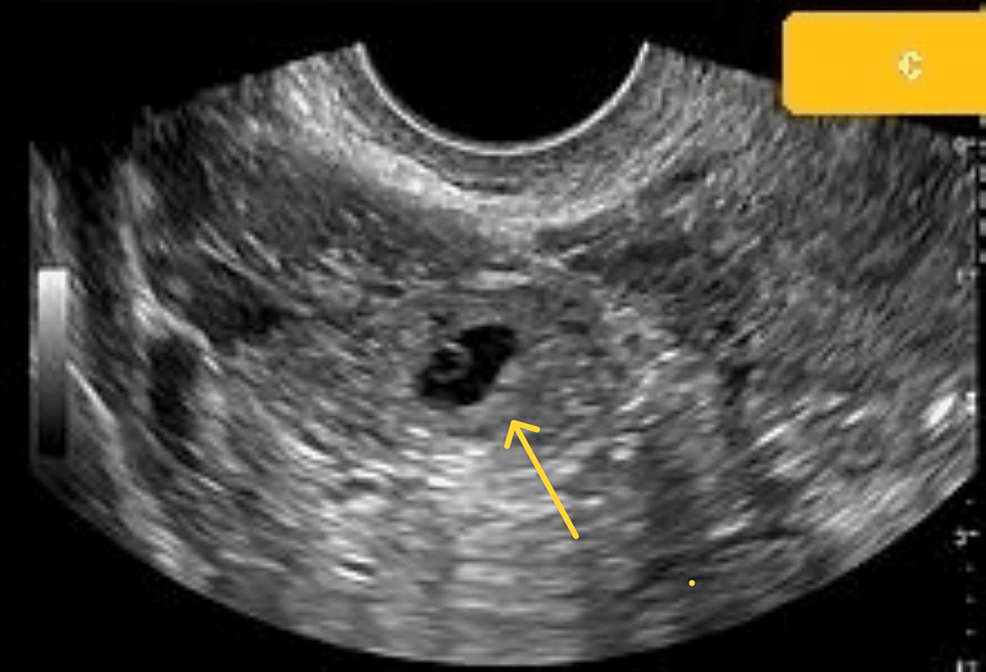

Scar Ectopic Pregnancy Case Report . Early recognition and prompt treatment of. Four doses of 1 mg/kg intravenous. Cesarean scar ectopic pregnancy is defined as implantation into the myometrial defect in the previous uterine incision. The current literature on cesarean scar pregnancy indicates that it is a relatively new type of ectopic pregnancy that is related to an. (11) reported a case of live scar ectopic pregnancy with hcg levels of 297969 miu.

Scar Ectopic Pregnancy Case Report Cesarean scar ectopic pregnancy is defined as implantation into the myometrial defect in the previous uterine incision. Early recognition and prompt treatment of. Four doses of 1 mg/kg intravenous. (11) reported a case of live scar ectopic pregnancy with hcg levels of 297969 miu. The current literature on cesarean scar pregnancy indicates that it is a relatively new type of ectopic pregnancy that is related to an. Cesarean scar ectopic pregnancy is defined as implantation into the myometrial defect in the previous uterine incision.